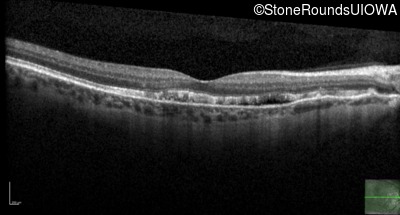

Age at visit: 58 years